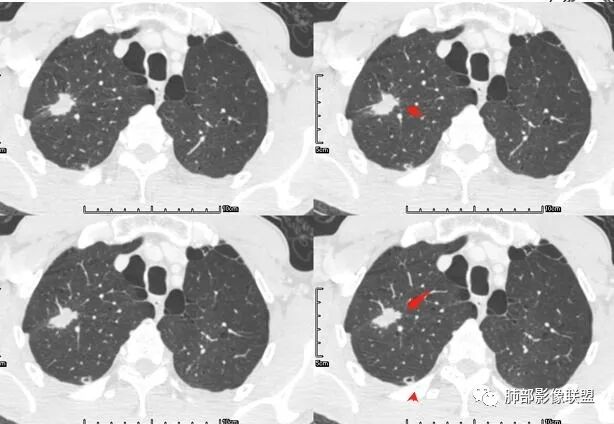

颈部淋巴结病检:腺癌;双肺多发薄壁囊腔性转移瘤;

来源于南京市第一医院 吴婧